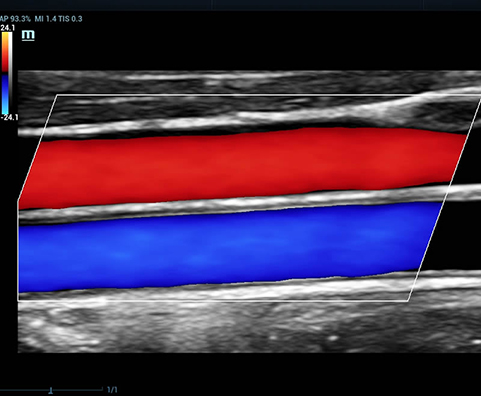

AdemÃĄs de una calidad superior de la imagen, el Resona 7 tambiÃĐn mejora las capacidades de investigaciÃģn clÃnica gracias al revolucionario V Flow para la evaluaciÃģn hemodinÃĄmica vascular y la adquisiciÃģn de planos mÃĄs inteligente a partir de un conjunto de datos 3D para el diagnÃģstico CNS fetal. Combinando el funcionamiento multitÃĄctil mÃĄs intuitivo basado en gestos y todas las funciones clÃnicas esenciales, el Resona 7 estÃĄ realmente encabezando nuevas ondas en la innovaciÃģn del campo del ultrasonido.